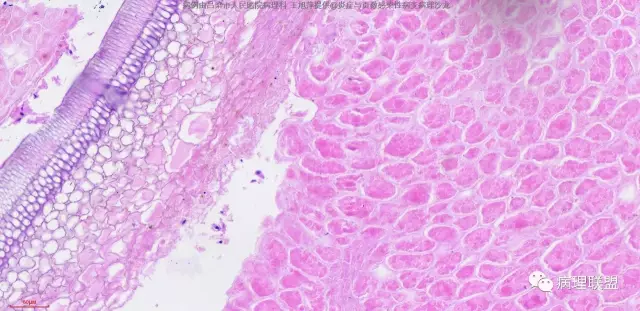

病人,男,60岁,腹股沟疝强行复位致肠管破裂,术中于肠系膜根部见结节一枚送检,肉眼灰红结节一枚,直径0.5cm。该病人于十年前曾行直肠癌根治术,麻烦各位老师,肠系膜结节考虑什么。(病例由吕梁市人民医院病理科 王旭萍提供,致谢!)